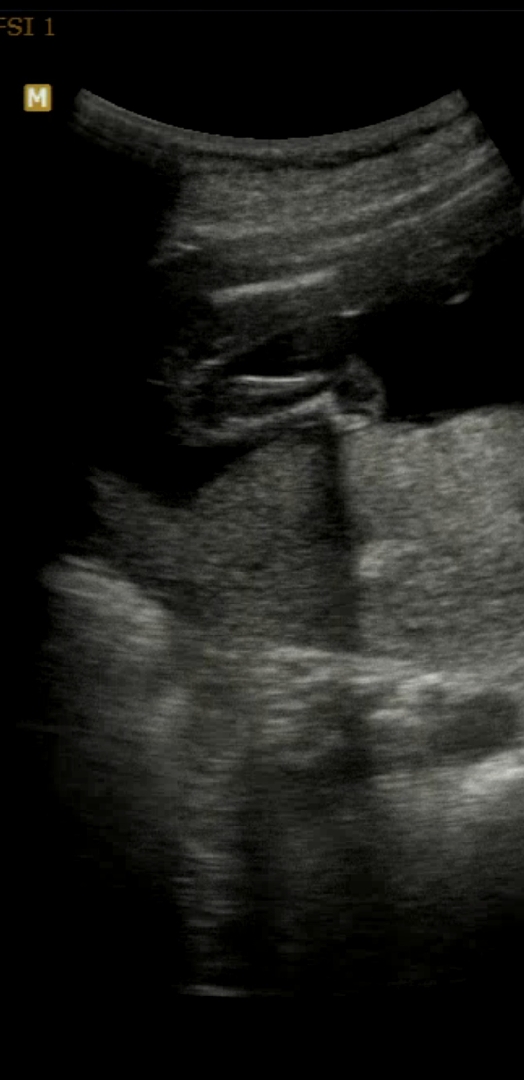

안녕하세요! 오늘이 딱 17주차 돌입인데 2차 기형아검사 하러갔다가 아가가 계속 움츠리고있어서 겨우겨우 다리사이를 보고왔어요! 쌤이 다리사이에 아무것도 없다며 엄마 닮은거같다고만 해주셨어요 딸이라고 돌려말씀해주신 것 같은데, 혹시 성별 반전이 흔한가용?? 이 맘때 쯤 아들이라면 다리 사이 존재감 뿜뿜이라고 그러는 분도 계시고, 지인 분은 20주차까지 기다려보자고 하시는 분도 계시더라구여..ㅠㅠ